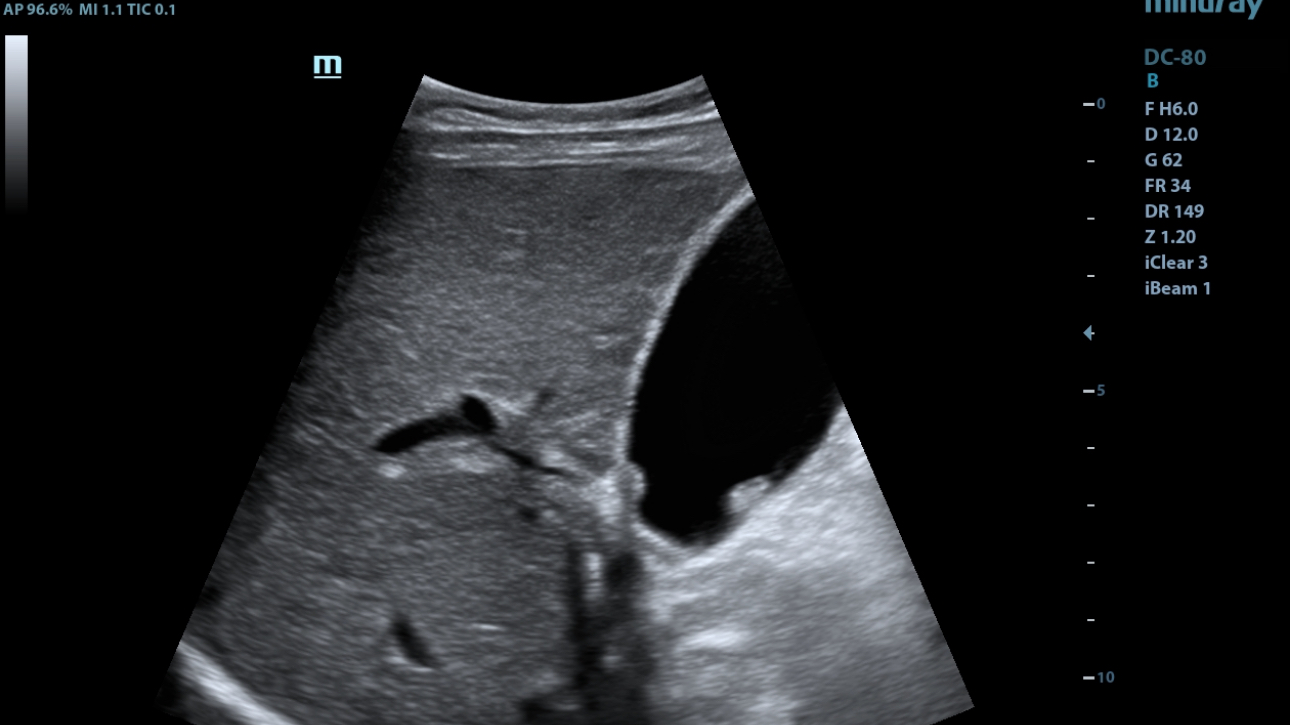

eXpress Clarity

More clarity at hand

To achieve excellent images with minimal effort is always the highest clinical priority and Mindray's endless pursuit. With continuous innovation of imaging and transducer technologies, X-Insight delivers express clarity as soon as the transducer touches the body.